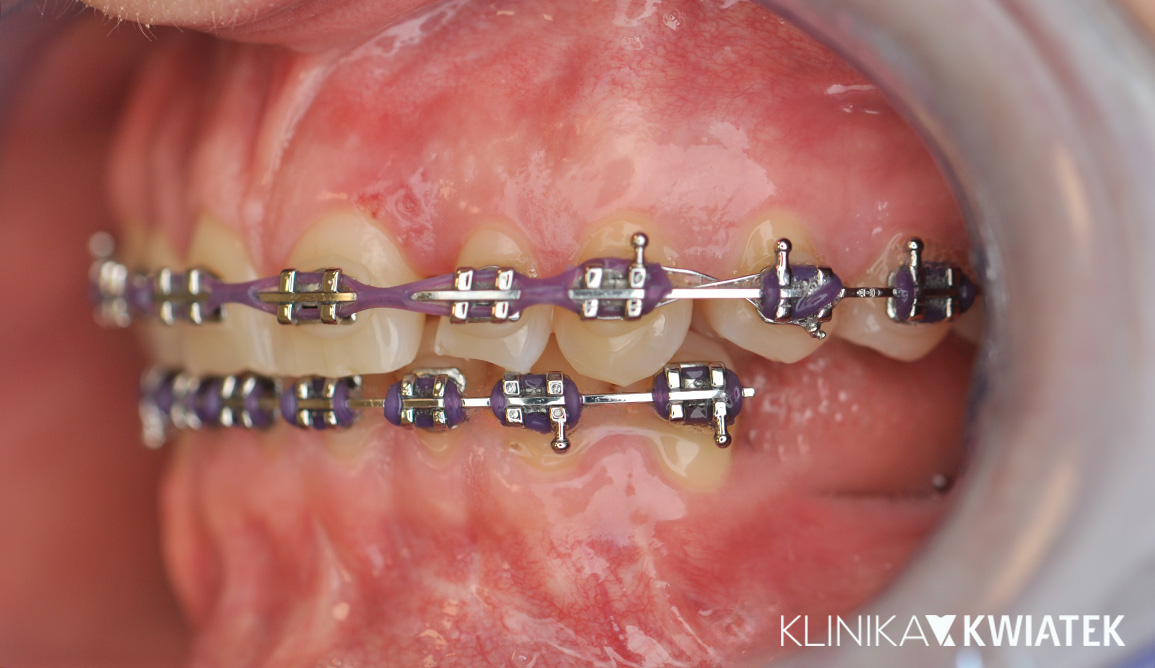

Zatrzymany kieł? Nowoczesna ortodoncja ma rozwiązanie!

27 letnia Pacjentka zgłosiła się do naszej kliniki z problemem wyrzynającego się nieprawidłowo kła górnego, przesuniętą linią pośrodkową i powiększonym nagryzem pionowym. Dzięki kompleksowej diagnostyce, leczeniu ortodontycznemu z zastosowaniem aparatów estetycznych i metalowych, wsparciu fizjoterapeutycznemu oraz regularnym higienizacjom udało się uzyskać prawidłową funkcję i estetykę uśmiechu. Efektem końcowym jest harmonijny zgryz, stabilne utrzymanie rezultatów dzięki retencji oraz piękny, zdrowy uśmiech.